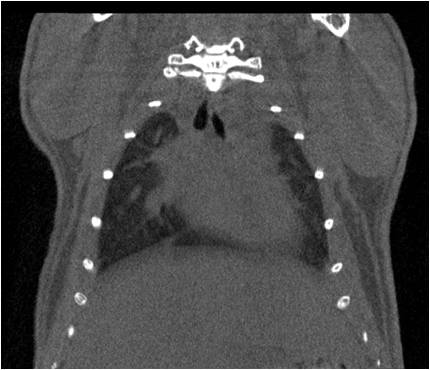

小鼠股骨

超高分辨率模式下像素大小為9μm。

A軸向和矢狀面顯示小鼠股骨結(jié)構(gòu)。

B用鈦材料植入的穿過骨頭的冠狀切片